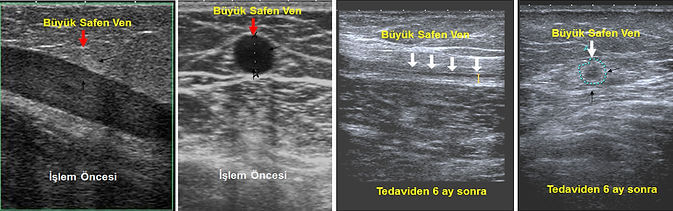

Varis hastalarında, varislerin kendisinden önce safen ven yetmezliği tedavi edilmelidir. Tedavide amaç hastalıklı olan safen veni iptal etmek ya da yok etmektir. Bunun için eskiden uygulanan yöntem ameliyatla safen venin kesilerek dışarı alınmasıdır. Günümüzde ise, iğne deliğinden girilerek safen ven lazer, radyofrekans, MOCA ya da yapışkan gibi yöntemlerle tahrip edilmekte, ve vücudun doğal mekanizmasıyla yok edilmektedir. Öyle ki, bu hastalara 6 ay sonra ultrason yapıldığında, safen ven ultrasonda bile güçlükle görülebilmektedir.

Lazer vs ile tahrip edilen safen toplardamarı, tedaviden sonra vücut tarafından küçültülerek yok edilir. Öyle ki, 6 ay sonra yapılan ultrasonda güçlükle görülebilir.